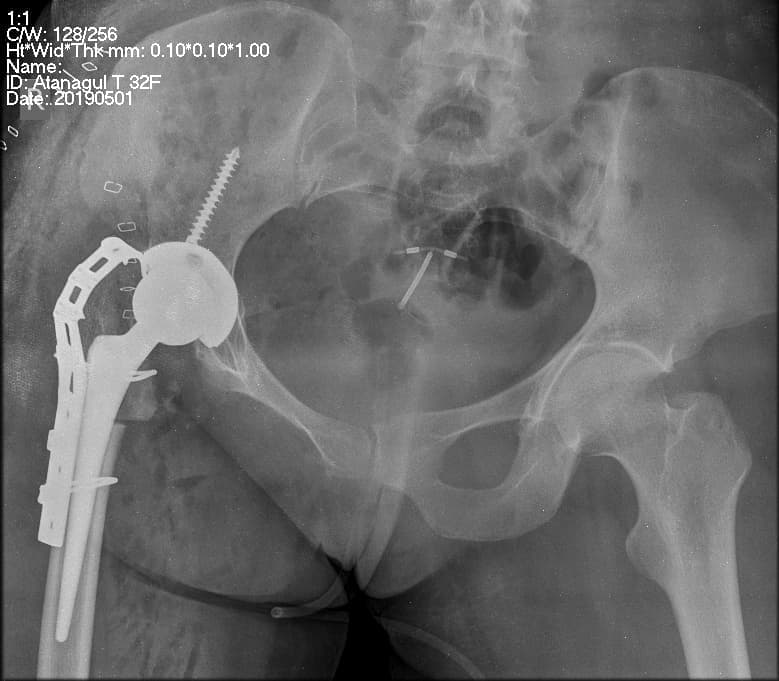

Түнхний үеийг хамарсан хавдарын үед хиймэл үе суулгах мэс заслын өмнөх болон дараах зураг

Түнхний үе бүтэн солих мэс засал (THA) image7Түнхний үе бүтэн солих мэс засал (THA) image8Түнхний үе бүтэн солих мэс засал (THA) image9